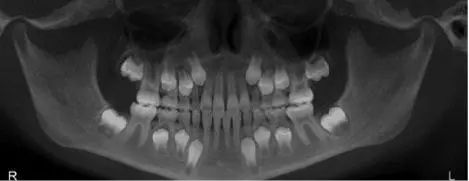

可是你想想看,孩子的恒牙可就长在牙床里面的。下面是一张幼儿的牙片,你们可以清晰的看到孩子恒牙的位置。

长期龋齿保不齐会像*荣大**这样牙根化脓,即便是不疼,长此以往的呕着脓水,恒牙的牙胚也必定会受到影响。严重的话,是可能导致恒牙胚坏死的。

而且,乳牙是恒牙发育的“向导”,恒牙会沿着乳牙的轨迹进行萌出,如果牙齿龋坏的厉害,乳牙过早丧失,就无法给恒牙留下足够的空间,萌出的时候就会参差不齐。到时候带着孩子矫正牙齿又是劳民伤财的修行,得不偿失啊。